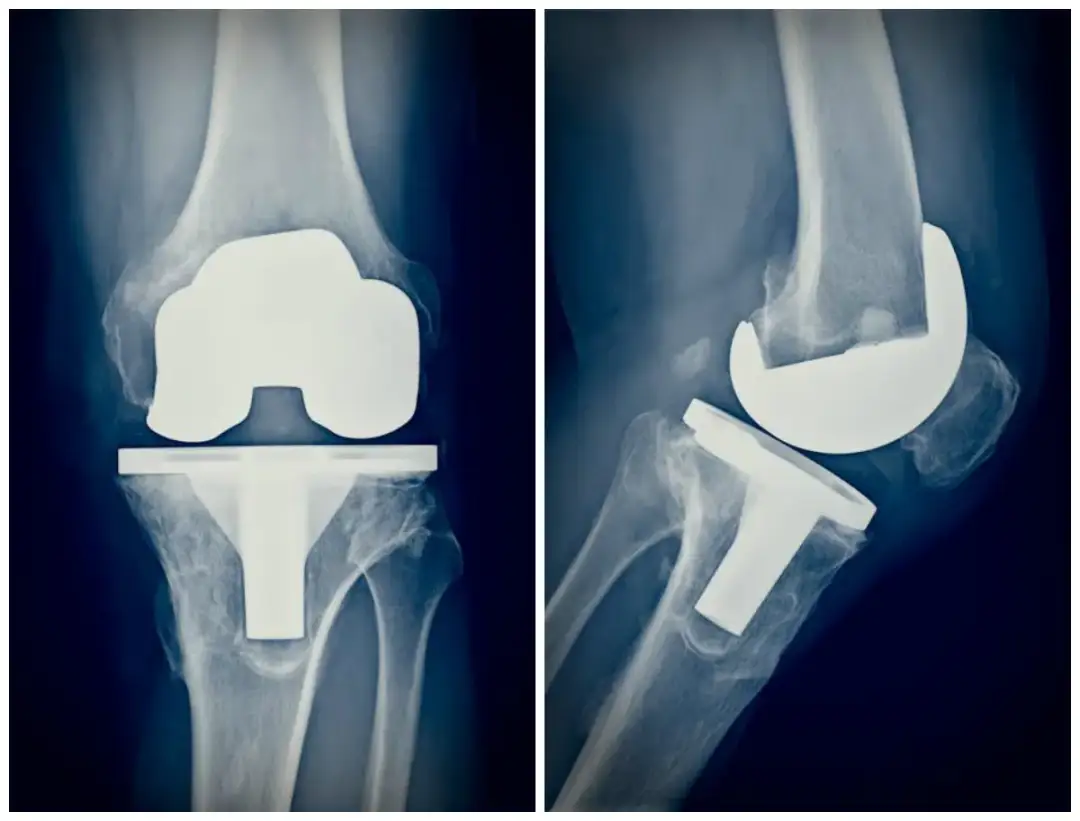

- Zdęcia rentgenowskie (RTG) pozwalają dokładnie ocenić stan stawu kolanowego.

| RTG kolana | Ocena stanu stawu i kości | Usunięcie metalowych przedmiotów |